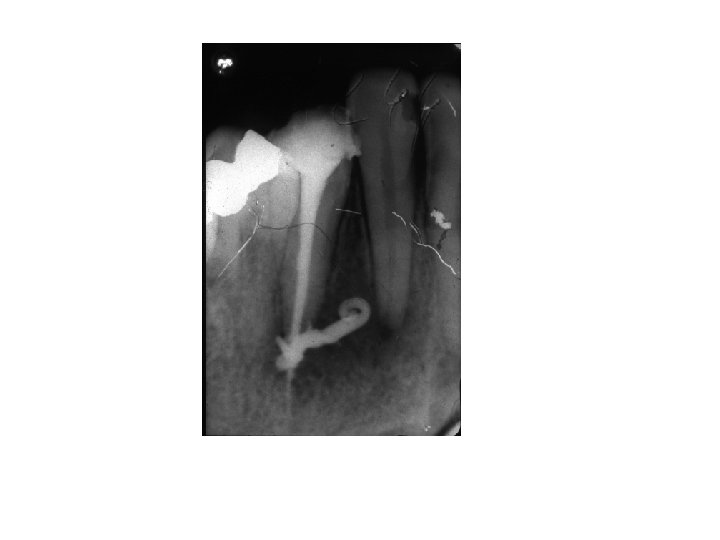

Wurzelbehandlung

Vor der Wurzelbehandlung Nach der Wurzelbehandlung